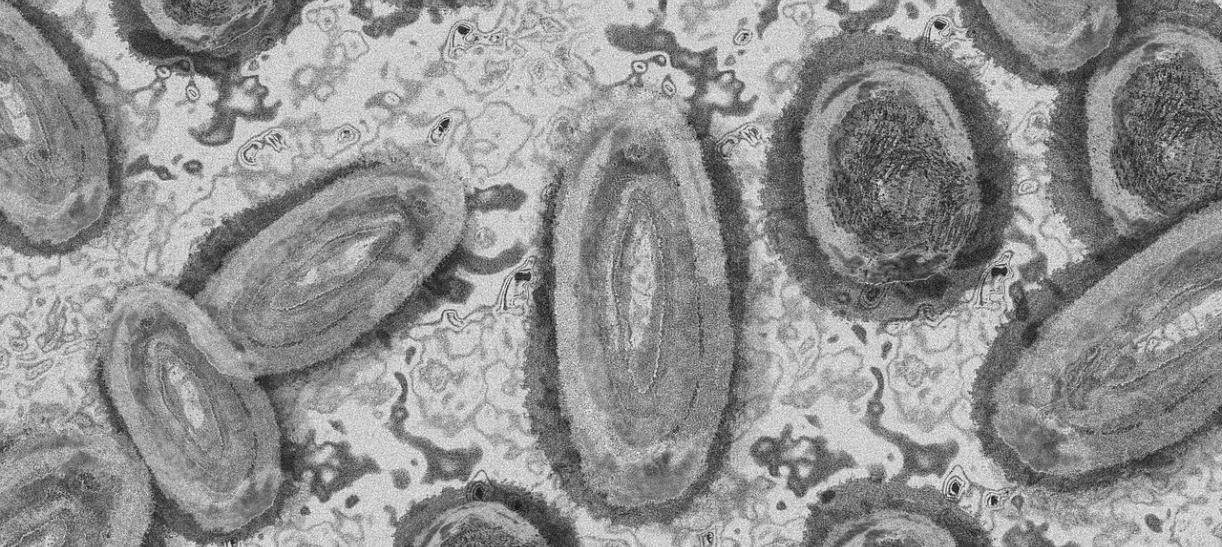

¿Qué se sabe de los casos de viruela símica en Colombia?

Después de varios análisis y pruebas médicas el Ministerio de Salud y Protección Social y el Instituto Nacional de Salud confirman tres casos de viruela símica en el territorio nacional.